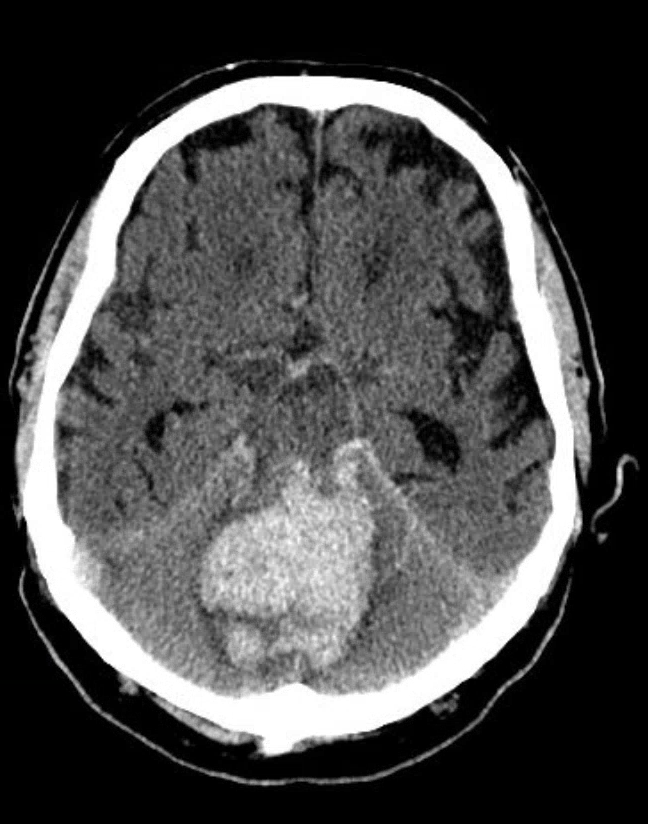

Ein irreversibler Hirnfunktionsausfall entsteht dann, wenn es zu einem Kreislaufstillstand im Gehirn kommt. Dies passiert in der Regel im Rahmen von Hirndruck. Der Schädel hat nur ein begrenztes Fassungsvolumen. Alle Dinge, die zu einer massiven Erhöhung des intrakraniellen Drucks führen, können einen IHA verursachen, da der Druck nicht nach außen entweichen kann. Intrakranielle Blutungen, vor allem Subarachnoidalblutungen, sind Hauptursache für die Entwicklung eines IHA.

In die erste Zeile trägt man die Diagnose ein. Dann muss man sich entscheiden, ob es sich um eine primäre Hirnschädigung (z.B. Blutung) handelt und ob diese supra- oder infratentoriell lokalisiert ist oder ob eine sekundäre (z.B. hypoxischer Hirnschaden nach Reanimation) Hirnschädigung vorliegt. Zur besseren Illustration hier noch mal die drei Klassiker der zum IHA führenden Diagnosen: